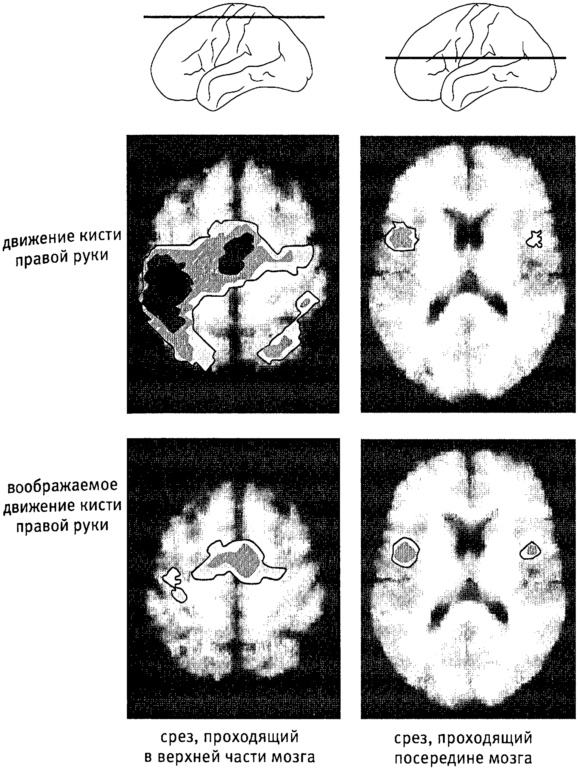

Рис. п.7. Результаты сканирования мозга во время реальных и воображаемых движений.

На схемах вверху показано, как проходят срезы мозга (в верхней части и посередине), на которых видна мозговая активность.

На верхних срезах показана активность, наблюдаемая, когда испытуемый двигает правой рукой, а на нижних – активность, наблюдаемая, когда испытуемый только представляет себе, что двигает правой рукой.